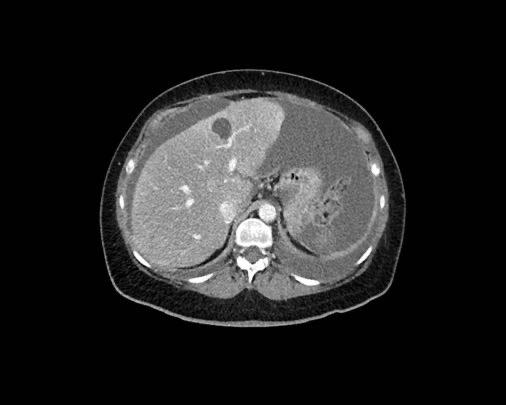

Cổ trướng

Sự hiện diện của cổ trướng là một dấu hiệu đáng lo ngại, do các nốt phúc mạc sản sinh ra dịch này và do đó có thể là gợi ý đầu tiên cho thấy ung thư phúc mạc (PC) đang hiện diện.